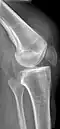

Quadriceps tendon rupture in plain X-ray -

Quadriceps tendon rupture in plain X-ray: Incomplete rupture with haematoma in tendon. -